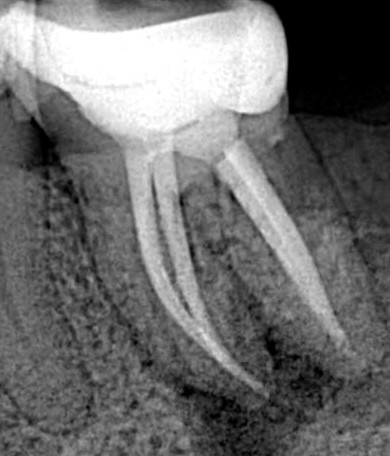

2) перепломбировка корневых каналов под микроскопом; |